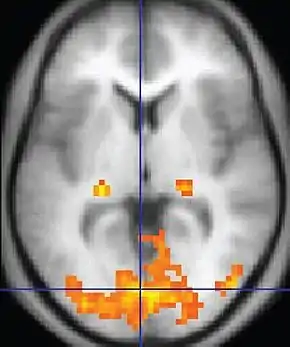

| Functional MRI (fMRI) | Blood-oxygen-level dependent imaging | BOLD | Changes in oxygen saturation-dependent magnetism of hemoglobin reflects tissue activity.[86] | Localizing brain activity from performing an assigned task (e.g. talking, moving fingers) before surgery, also used in research of cognition.[87] | ![]() |